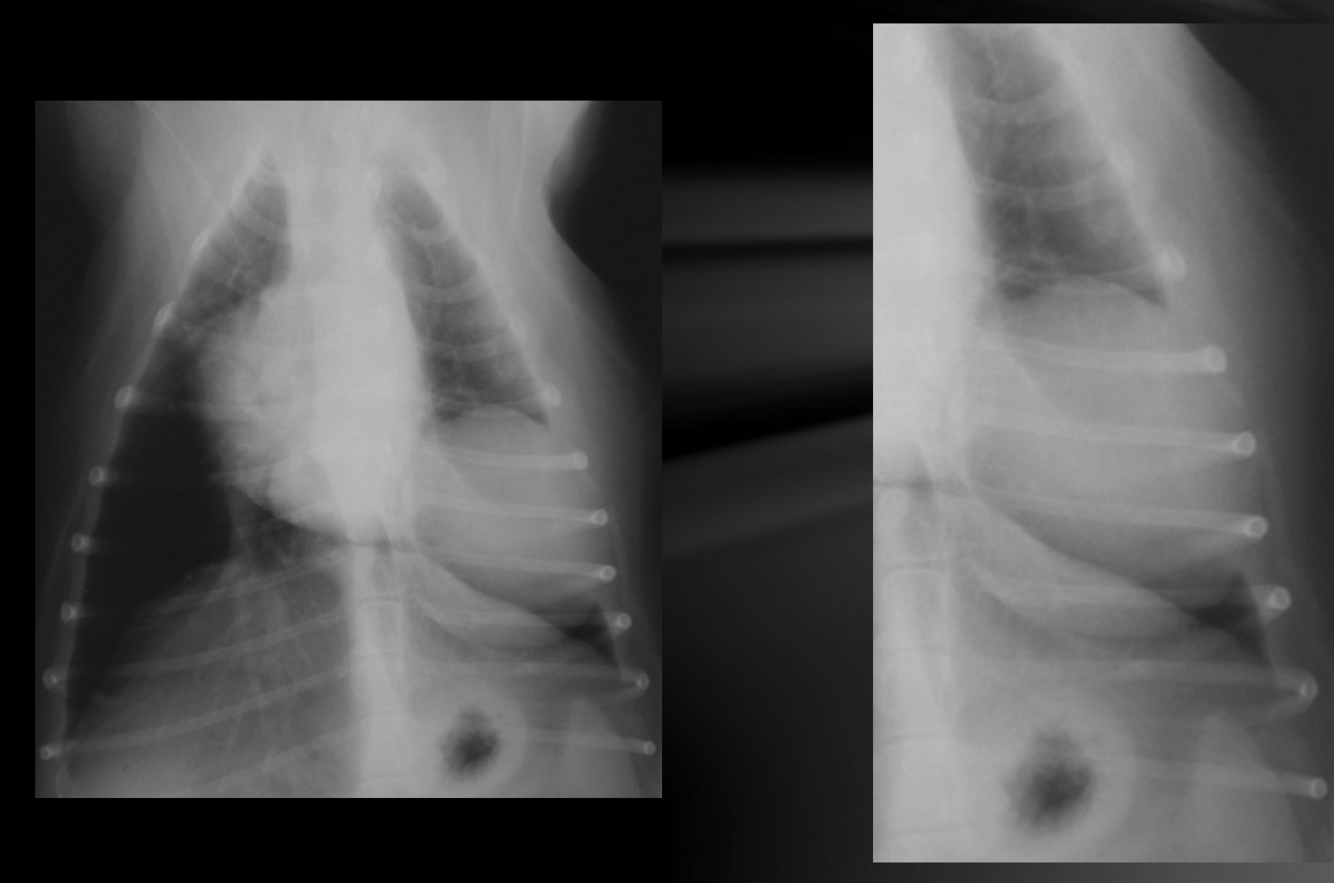

What is important regarding the ribs in these radiographs?

young dog; costal cartilages have not mineralized at all